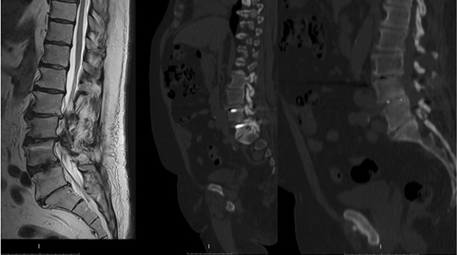

Two years after the initial decompression and stabilization at the L4-L5 level, the patient presented with renewed low back pain of insidious onset, gradually increasing over several months. The pain was described as deep and aching, localized higher in the lumbar region than before, with occasional radiation to the anterior thigh, but without distal leg symptoms. The patient reported stiffness and fatigue in the lower back, aggravated by prolonged standing or walking, and relieved by rest or sitting. No bowel or bladder symptoms were noted. On examination, lumbar movements were globally restricted, particularly extension, which reproduced pain in the upper lumbar region. Palpation elicited tenderness over the L2-L3 interspinous space, with paraspinal tightness. No step-off deformity was palpable at the previous operative site. Neurological examination showed mild weakness in hip flexion and reduced sensation over the anterior thigh (L3 dermatome), with preserved knee and ankle reflexes. Pain distribution corresponded to L3-L4 dermatomes. At this admission his VAS was 8 and ODI 80 %. The patient’s pain remained refractory to conservative management, including epidural steroid injection. MRI and CT scans revealed adjacent segment degeneration with Meyerding I listhesis at L3-L4, right-sided L3 disc herniation, mediolateral L2 disc herniation, and bilateral foraminal stenosis. The previously fused L4-L5 level remained stable, with no hardware complications (Figure 2). Revision Minimally Invasive (MIS) TLIF was therefore performed, involving the elongation of the previous instrumentation to L3 and L2, included L2 and L3 discectomies with insertion of PEEK cages filled with bone graft.

Figure 2: Showing Grade I spondylolisthesis at the L3-L4 level with severe spinal canal stenosis at the L2-L3 and L3-L4 levels, and radiological signs of fusion at the L4-L5 disc space.